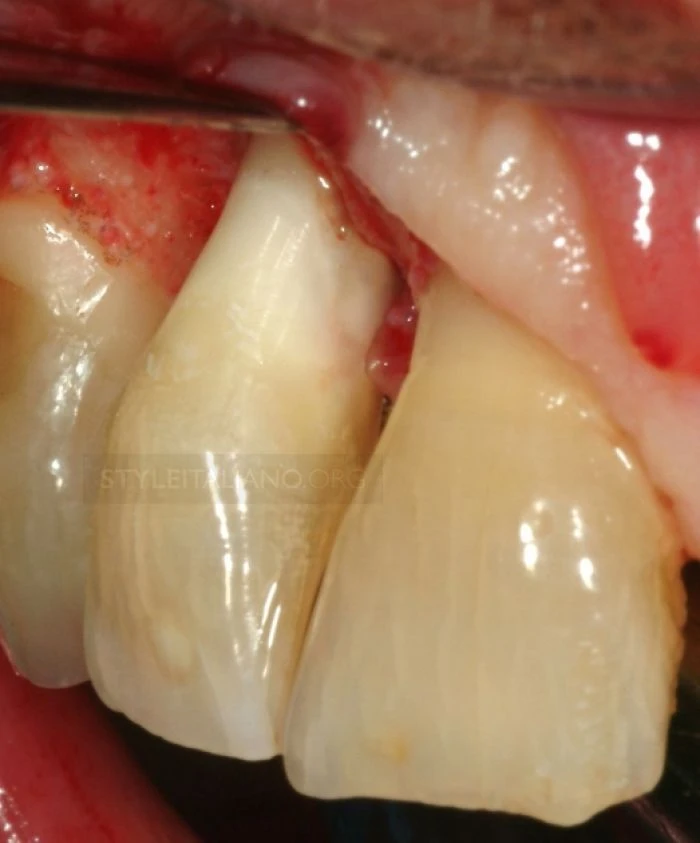

Phần răng bị gãy phải được ngâm trong nước muối sinh lý (0.9% NACl) tương tự như khi xử lý một chiếc răng gãy chân khác, chúng ta không được đánh bóng vết nứt hay răng để tạo điều kiện dán dính tốt hơn(6). Quan sát mảnh răng gãy có thể thấy bề mặt vết gãy bị vát ít nhất là 3mm về phía chóp so với mặt trong.

Hình dạng vết gãy thế này làm cho việc cách ly để điều trị tủy và gắn răng trở lên rất phức tạp.

Nhìn từ mặt bên